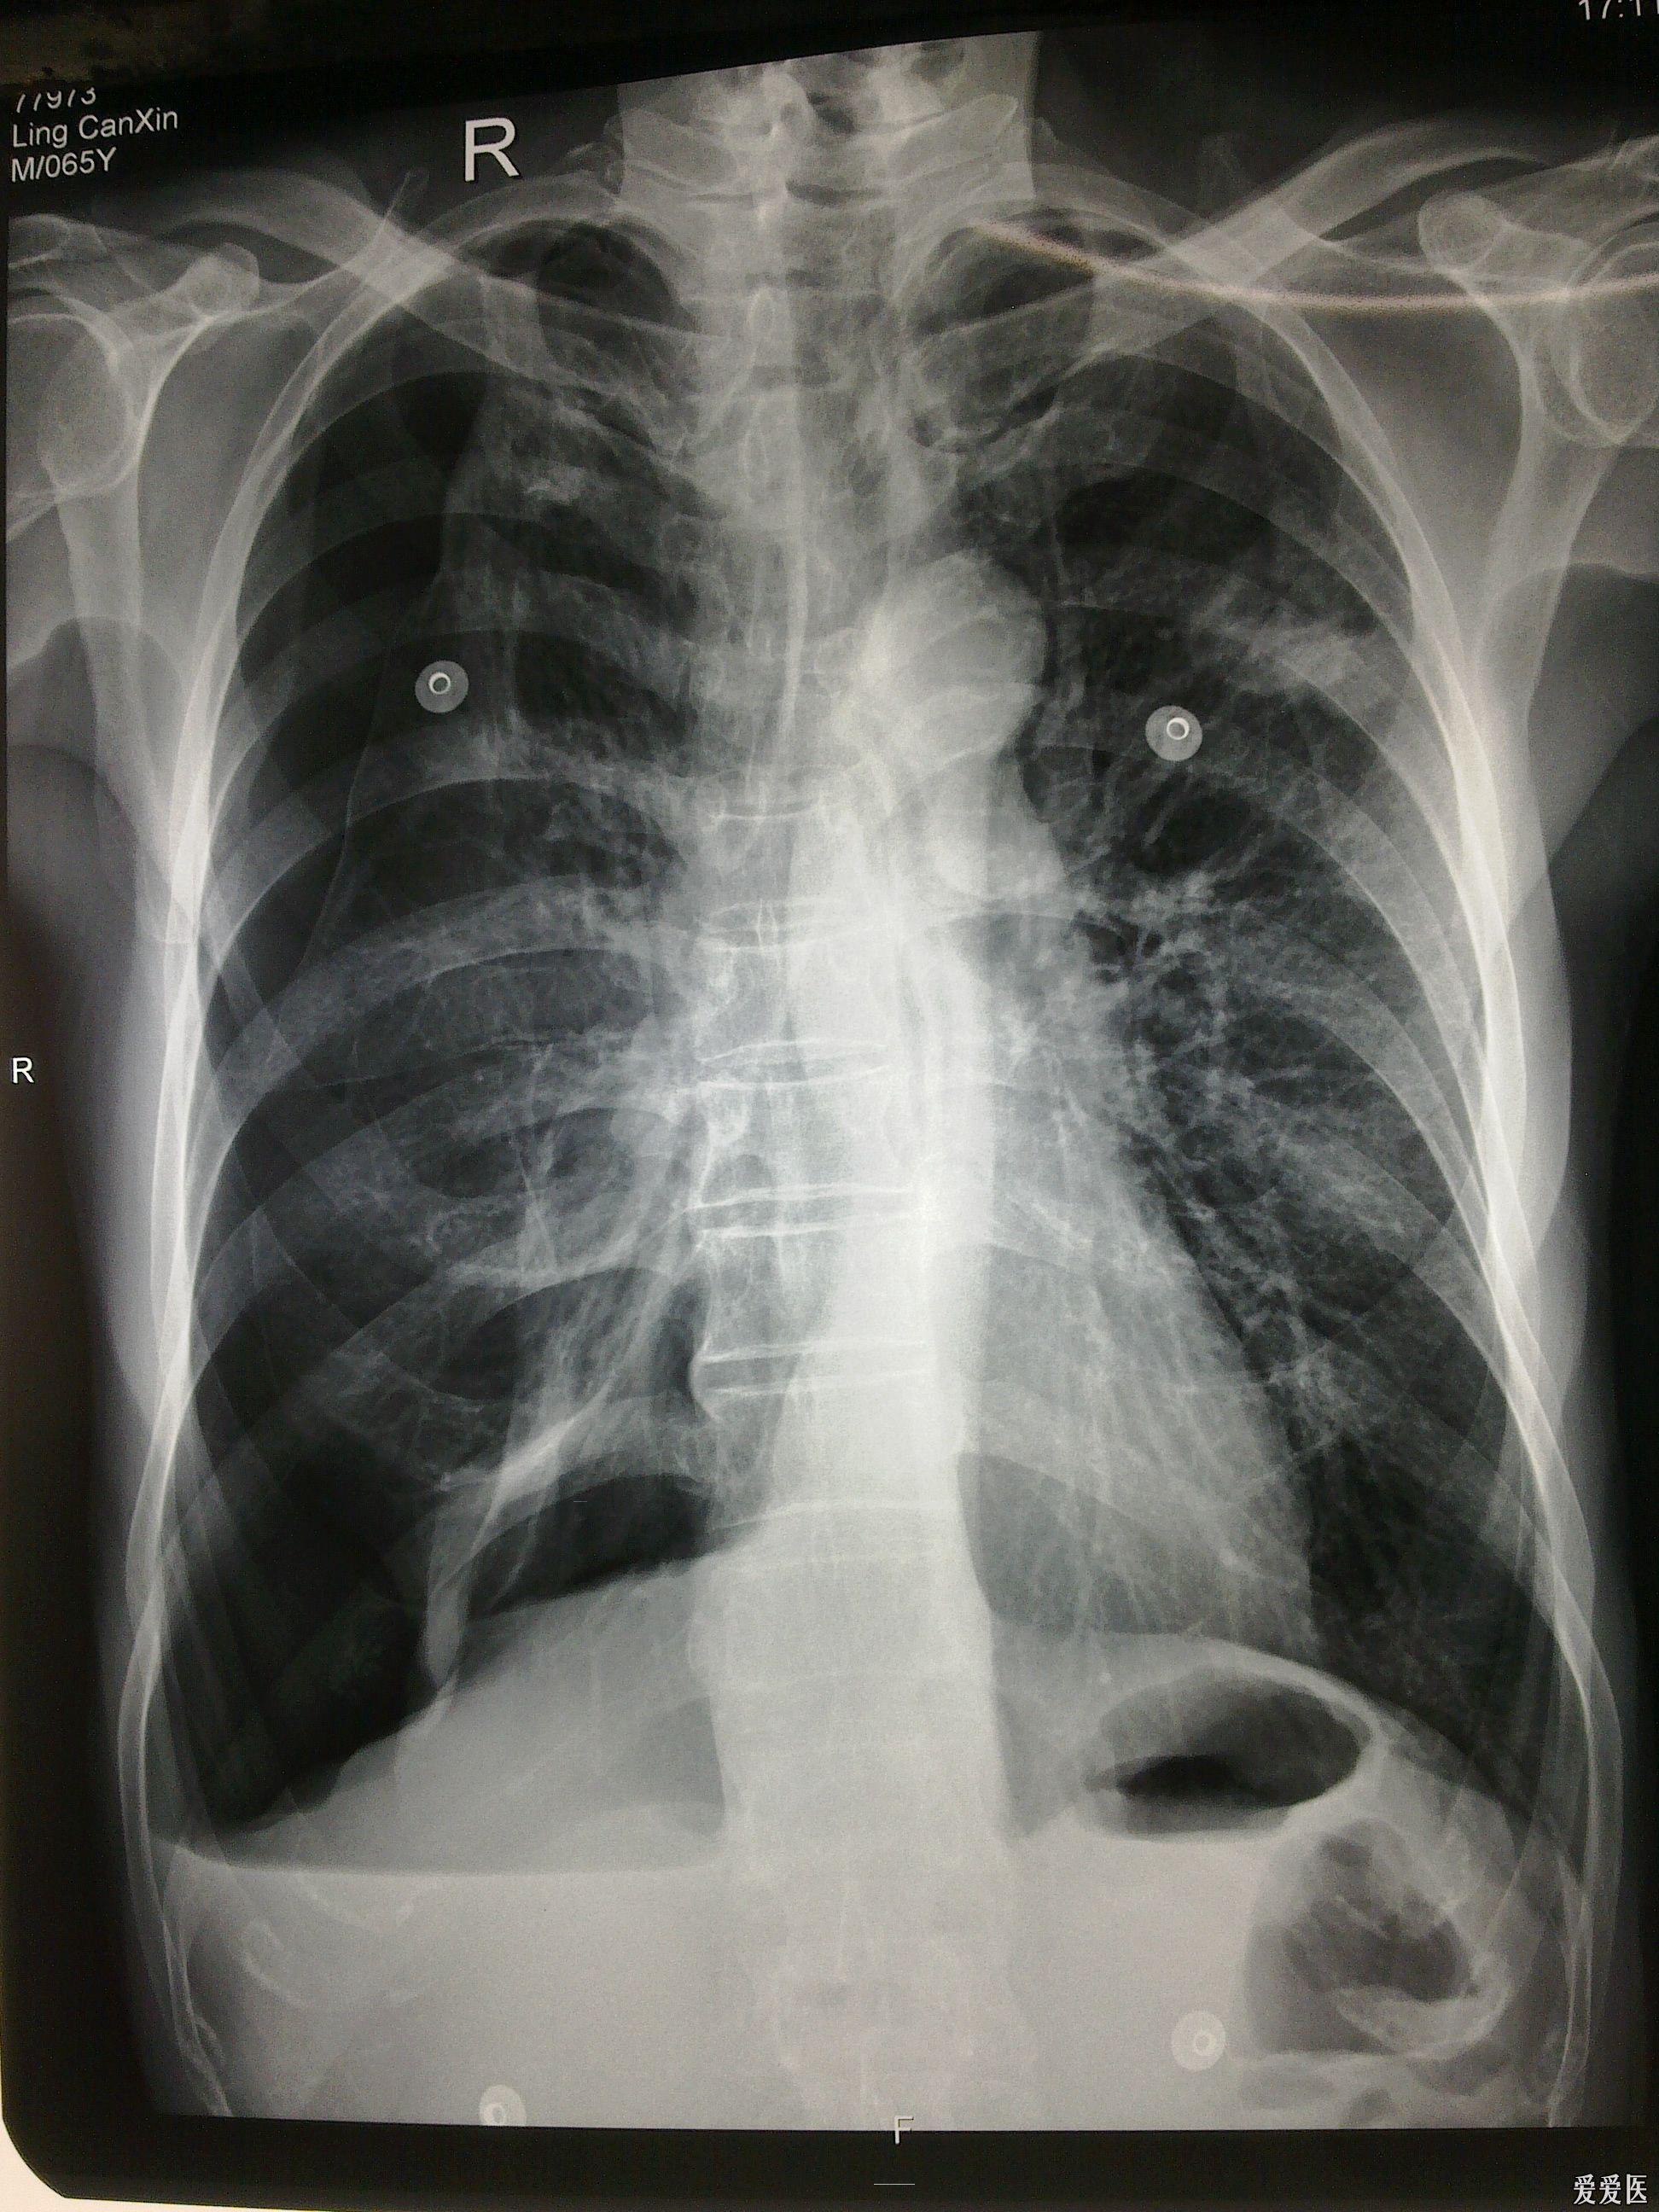

气胸患者胸部x线表现

一侧气胸肺严重压缩